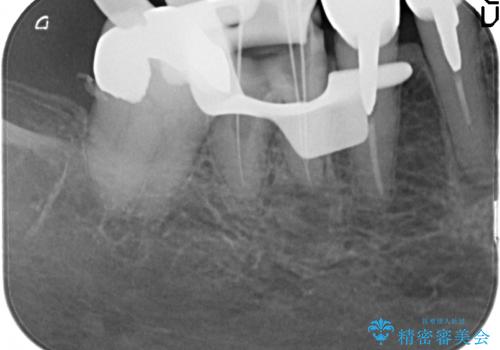

(神経のない歯)再根管治療→ファイバーコア→ジルコニアクラウン

治療中写真から分かる通り、インレーは詰め物周囲に歯が残存し、クラウンは残存した歯周囲を被覆しています。

神経のない歯は、「歯の破折防止」「根管系への再感染防止」の観点から基本的にクラウン治療をお勧めします。